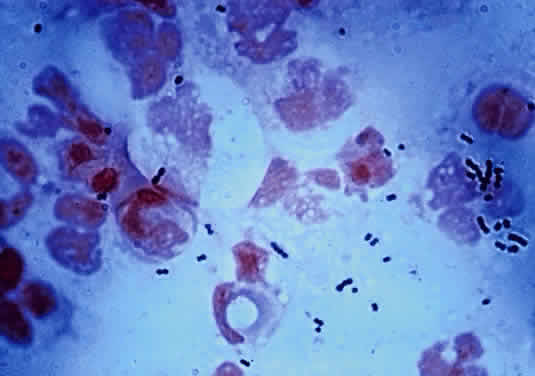

During microscopic examination, staphylococci almost always appear Gram-positive, are spherical with a mean diameter of approximately 1 mm, and are seen extracellularly. Old cultures or scrapings from antibiotic-treated cases may show Gramnegative staining characteristics. Although grape-like clusters are frequently seen in scrapings or smears from nonocular tissues, these are unusual in scrapings from corneal ulcers, in which single cocci or clusters of two to six cocci are observed. Two species, S. epidermidis and S. aureus, cannot be distinguished by Gram stain; however they show distinct characteristics in culture. In general the staphylococci are easily cultured on standard bacteriologic media (see laboratory section) and grow rapidly in incubation at 37°C. They do not have a distinctive odor and grow in the presence or absence of oxygen. Typical colonies are round, flat, smooth, and several millimeters in diameter by 48 hours (Fig. 1). S. aureus colonies show beta hemolysis (clear zones of hemolysis on blood agar) and some degree of pigmentation (light cream to golden yellow). In contrast, S. epidermidis colonies are usually nonhemolytic and rarely exhibit pigmentation.

The microscopic appearance of all streptococci, except for pneumococcus, is similar. Smears taken from culture material show Gram-positive cocci in chains of varying lengths. Scrapings taken directly from infected ocular tissues may not demonstrate the chain effect, and differentiation from staphylococci may be difficult (Fig. 4). The morphologic characteristics of the Staphylococcus and Streptococcus organisms are outlined in Table 3.